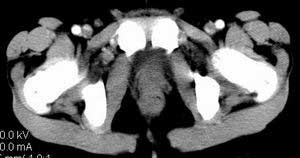

| 患者,男,9岁,因右下腹包块入院,血象不高,不规则发热,常超40度。 平扫: ![]() ![]() ![]() ![]() ![]() ![]() ![]() ![]() ![]() ![]() ![]() ![]() ![]() ![]() ![]() ![]() ![]() ![]() 增强: ![]() ![]() ![]() ![]() ![]() ![]() ![]() ![]() ![]() ![]() ![]() ![]() ![]() ![]() jiajie发言:骶椎右前区不规则软组织肿块,边缘光整,密度均匀,增强后均匀强化,右腹股沟区可见肿大淋巴结,临床有时发热,考虑淋巴瘤,儿童盆腔肿瘤应与神经母细胞瘤和横纹肌肉瘤鉴别。 longzhanghui发言:印象:盆腔右后壁不规则软组织肿块,并向前延伸.似为多个肿块融合,呈中等强化.初步考虑淋巴瘤. 听蝉观竹发言:右侧髂内、外组淋巴结肿大,从其形态和融合的情况看,同意大家意见-----考虑恶性病变,但是9岁男孩还要注意检查睾丸情况,有无隐睾? 常常类似情况是隐睾发生精原细胞瘤淋巴结转移,这个病例也要注意这一点!!! 广东凌发言:大家好,在这里我想说一下个人观点,我建议上传图片的同志能否辛苦一点就是把病史和图片都上传完整一点,比如这个病人的腹膜窗,并且这个病人的肠道的准备也是不怎么好,就从现有的质料看:病灶属于淋巴结肿大当无大的争议,有融合趋势,其内无坏死,边缘强化为主,故考虑:淋巴瘤!建议用腹膜窗看一下和肠道的关系! 阿圣发言:病灶属于淋巴结肿大当无大的争议,有融合趋势,其内无坏死,边缘强化为主,故考虑:淋巴瘤 结果是:淋巴瘤 病例来源:ct762。由宁静致远发布: http://www.radinet.com.cn/forum_view.asp?forum_id=4&view_id=2182 |